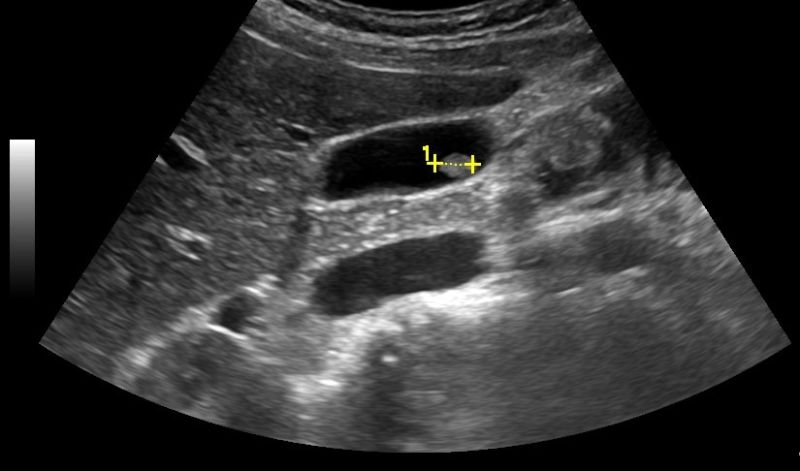

- Σε περίπτωση νεφρολιθίασης: βαθμός διάτασης του πυελοκαλυκικού (αποχετευτικού) συστήματος του νεφρού, διερεύνηση της εντόπισης του λίθου (στο νεφρό, τον ουρητήρα ή την ουροδόχο κύστη)